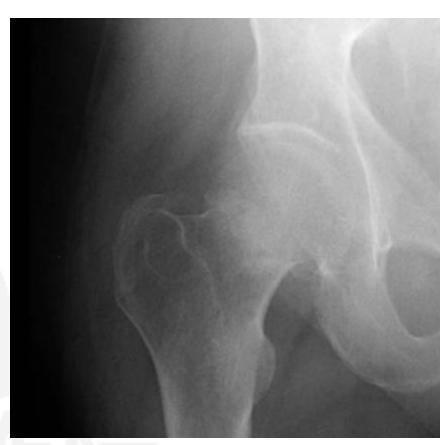

Intertrochanteric Fracture

Diagnosis: Intertrochanteric fracture of neck of femur Treatment: Dynamic hip screw or proximal femoral nail